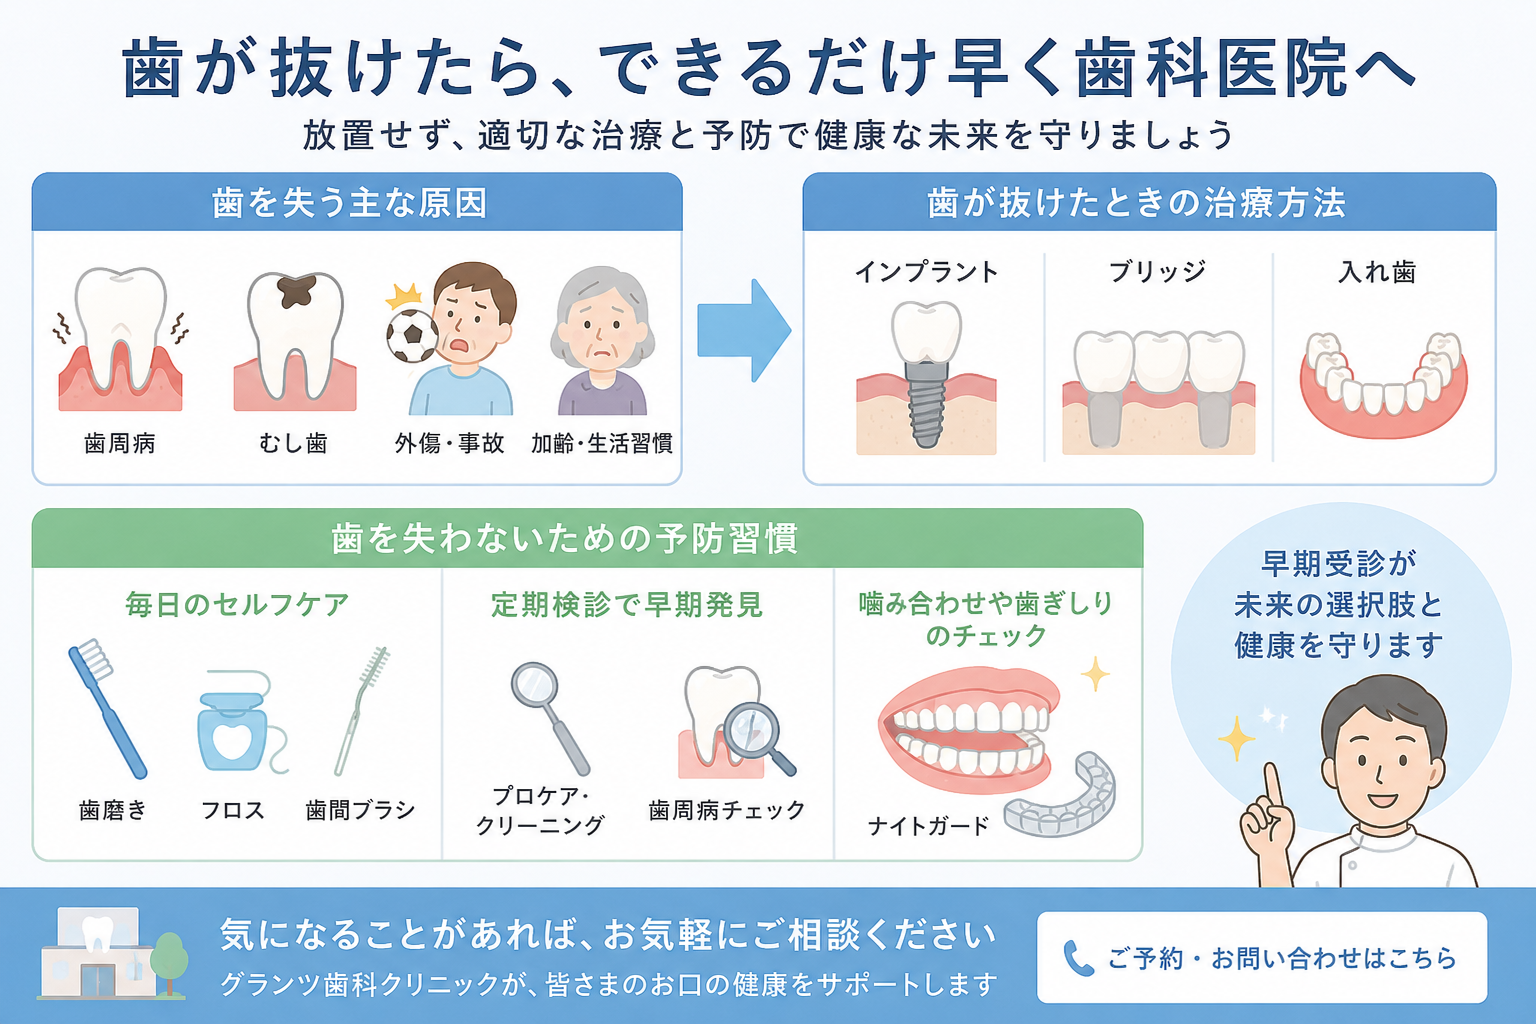

歯周病の治療として、まず最初は歯磨きの見直しからです。お家で出来る歯周病のケアは歯磨きです。

磨き残し(プラーク・歯垢)を除去することで、歯茎の炎症を軽減できます。

歯垢が石灰化したものが歯石です。

歯石はハブラシでは取れませんので、歯医者さんでの歯石取りが必要です。(※稀にご自身で器具を使って取った、という方がいらっしゃいますが絶対におやめ下さい。)

歯石取りをしても、骨にまで感染が及んでいる場合、骨の再生は自然には起こりません。部分的(垂直的)に骨が吸収されている場合、数年で歯を失う確率が高くなります。

その際は【歯周組織再生療法】が適応になります。部分的に骨を再生させる事ができるということです!

歯周組織再生療法とは、

歯周病により歯の周りの組織を回復させる(出来るだけ元の状態に近づける)処置です。

当院では、パノラマというレントゲンだけでなく、CTにて、立体的にどういう骨の形態をしているのか確認した上で慎重に診査診断を行います。

そして、歯周組織を再生させる専用の薬剤を取り寄せたり、人間の体になじみの良い骨を使用して歯周外科処置を行います。

失って初めて気付く歯の大切さ。できれば歯があるうちに、健康なうちからケアすることをおすすめします。

姫路駅前グランツ歯科では、患者様の理想を叶えることを目的に、機能的にも審美的にも回復する質の高い治療をしております。お一人お一人によってベストは異なりますので、まずはお電話にて ご相談ください。